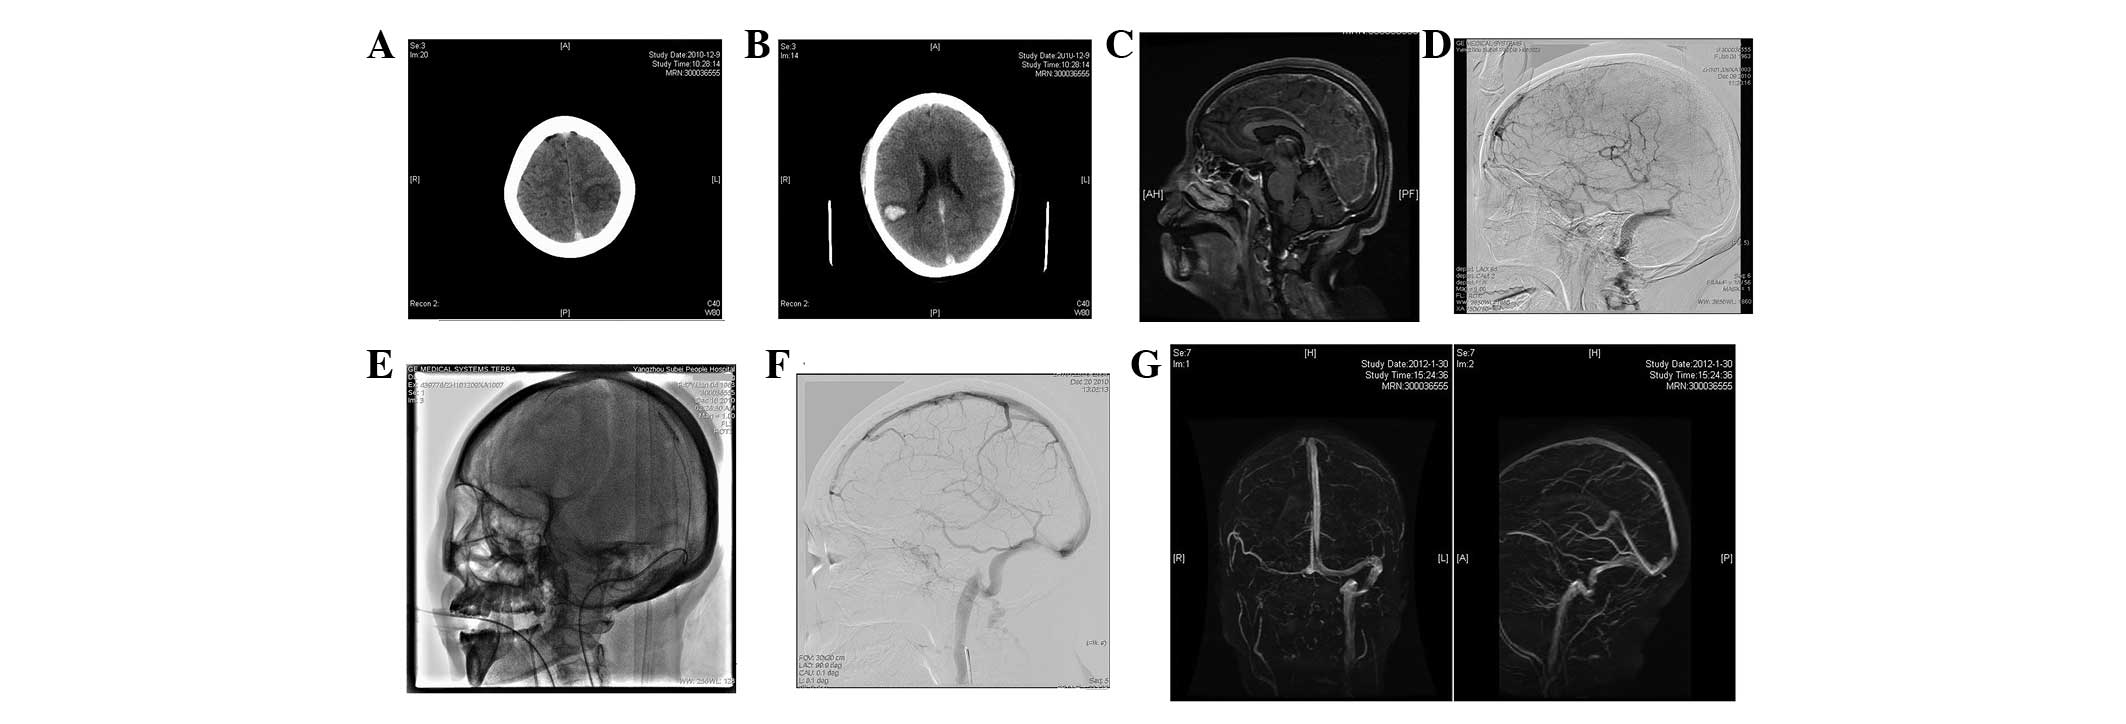

Typical case 2 (female, 21 years-old)

Headache with left limb weakness lasted for 5 days and unconsciousness lasted for 1 day prior to hospitalization. Physical examination revealed the GCS score to be 7. The patient had aphonia and both eyes gazed to the right side. The left nasolabial fold became shallow and MRI revealed that the bilateral thalami were infarcted, particularly on the right side (Fig. 2A). Enhanced imaging showed that thrombi existed in the straight sinus, left transverse sinus and superior sagittal sinus (Fig. 2B and C). DSA revealed that the left transverse sinus and straight sinus did not develop (Fig. 2D). The microcatheter was placed in the straight sinus via the left transverse sinus and the sacculus expanded during surgery (Fig. 2E–H). Awareness improved at day 2 following surgery, but the patient developed hypersomnia and aphasia. At day 3 after surgery, the patient regained consciousness and was able to have simple verbal exchanges. Left side muscle strength was at level 3 and right side muscle strength was at level 4. At day 9 following surgery, the patient’s speech was fluent, right side muscle strength was at level 5 and left side strength was at level 4+. MRI and MRV examinations at week 2 following surgery revealed that the disease was in remission and the superior sagittal sinus and straight sinus had recanalized (Fig. 2I–K). At week 6 after surgery, the patient’s muscle strength recovered and MRV showed that the straight sinus had recanalized, whereas the left transverse sinus was closed (Fig. 2L and M).

Figure 2

Catheter-directed thrombolysis in the straight sinus. (A) Head MRI T2 weighted image showed that the bilateral thalami were infarcted and the right side was more severe; (B) thrombus in the straight sinus as shown by enhanced MRI; (C) thrombus in the left transverse sinus and superior sagittal sinus as shown by enhanced MRI; (D) DSA showed that the left transverse sinus and straight sinus did not develop; (E) guidewire entered the transverse sinus during surgery; (F) sacculus expanded during surgery; (G) left transverse sinus was open during surgery; (H) microcatheter was placed in the straight sinus; (I) microcatheter angiography revealed that the straight sinus developed following thrombolysis; (J) 2 weeks after surgery, review of the T2 weighted image showed that disease extent of the thalamus had reduced; (K) enhanced imaging showed that the superior sagittal sinus and straight sinus were open; (L) MRV showed that the superior sagittal sinus and straight sinus were open; (M) 6 weeks after surgery, MRV showed that the straight sinus was open but the left transverse sinus was closed. CT, computed tomography; MRI, magnetic resonance imaging; DSA, digital subtraction angiography; MRV, magnetic resonance venography.